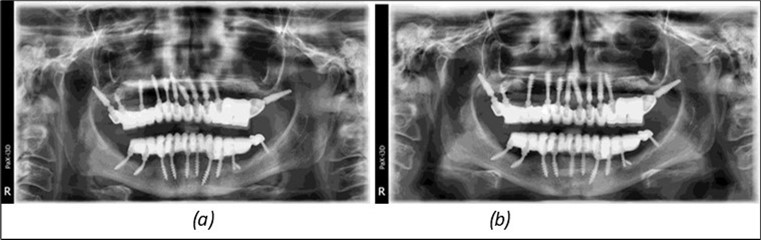

June 2022: Patient presented to our clinic for immediate-loading implant treatment At the time of presentation in 06. 2022, radiologically, advanced peri- implantitis is observed around the implants, with loss of native bone in the affected distal areas (Figure 1)

Figure 1.Panoramic overview picture before rehabilitation 06.2022

Figure 3.Panoramic pictures after removal of implants affected by peri-implantitis, extractions, alveolar crest regularization, and insertion of corticobasal and TPG implants (07.2022)

Figure 14.Rx panoramic final situation control: (a) Panoramic X-ray with the addition of a distal BCS implant in quadrant 3 at 11.2022; (b) Control X-ray, 10.2023.